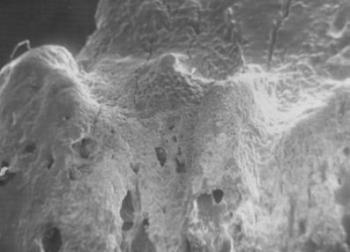

39. ábra. Az enthesopathiás terület áttekintő elektronmikroszkópos képén változó nagyságú csonttarajok ábrázolódnak. SEM 40× nagyítás